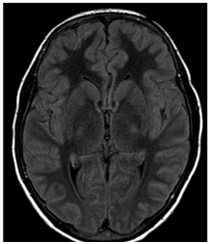

A CT (Computerized Tomography) scan of the skull was requested and did not show any signs of intracranial hemorrhage. Subsequently, magnetic resonance imaging (MRI) of the brain was performed, evidencing two focal areas of high signal in DWI in bilateral centrum semiovale (Figures 1‒5). Considering that the treatment wasn`t finished and still consisted in high and continuous doses of MTX, aminophylline was introduced in order to prevent/reverse the effects of the subacute ischemic event due to the medication.

Figure 1 Focal and symmetrical regions of restricted diffusion on DWI on centrum semiovale.

Figure 4 Focal and symmetrical regions of restricted diffusion on DWI on centrum semiovale.

The imaging modality of choice is MRI, because it has a high sensitivity and specificity for relevant differential diagnosis such as cerebral metastases, opportunistic infection, hemorrhage, dural venous obstruction or ischemic infarction. In acute/subacute stroke like MTX-induced neurotoxicity, DW and T2 hyperintensities are typically located in the periventricular white matter, particularly in the centrum semiovale, and often seen only on DWI (diffusion weighted images).12